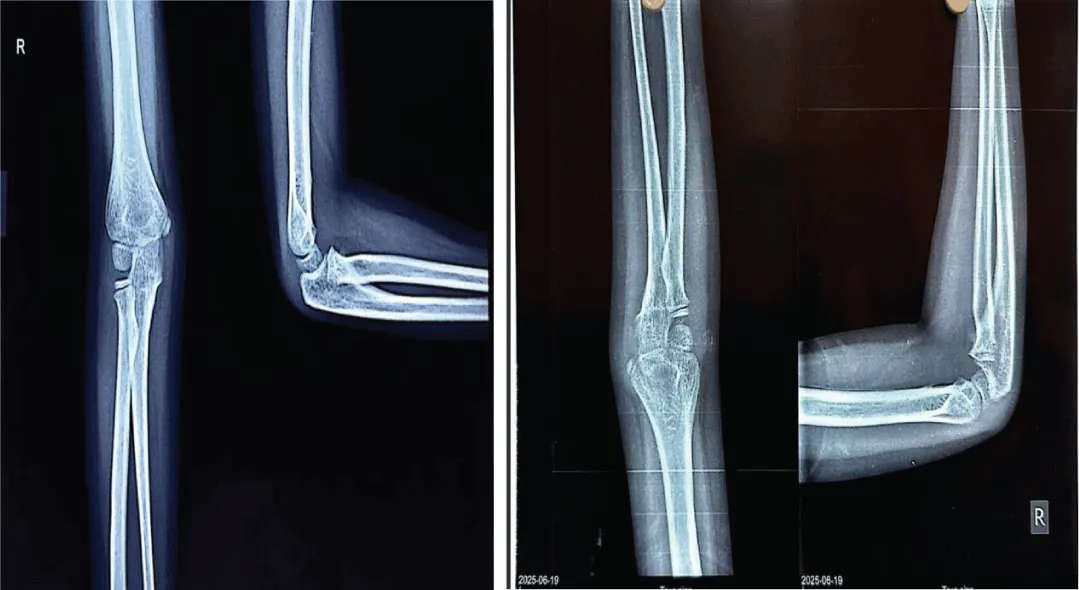

A mother with 6 year old female child presented to our Orthopedic Out Patient Department. She had not been able to move her right elbow in full range with restricted active and passive movements and appeared distressed. According to the informant (mother), she had been apparently well 2 months back when she was hit by rear wheels of a tractor while playing on the roadside. She developed pain and swelling in the elbow and was immediately rushed to the nearby hospital. Routine investigations, CT scan of abdomen and pelvis and X-ray of right elbow and hand were done. (Figures 1-3). All reports were normal except X-ray arm diagnosing undisplaced low lying supracondylar fracture of the right humerus (Figure 3). The child was admitted to the hospital and right upper limb was immobilized in an above-elbow plaster slab, with the elbow in 90o flexion (Figure 4). She was discharged after 4 days with reportedly normal radiographic findings.

However, the child continued to experience persistent pain and stiffness in the elbow region, progressively limiting the range of motion. This prompted another hospital visit, during which an X-ray of the right elbow was obtained (Figure 5). Subtle calcific changes-early signs of heterotopic ossification-were present but went unnoticed. Physiotherapy was initiated under the assumption of post-immobilization stiffness. However, within a few days of physiotherapy, the patient developed worsening stiffness and a painful, enlarging subcutaneous lump in the elbow region.